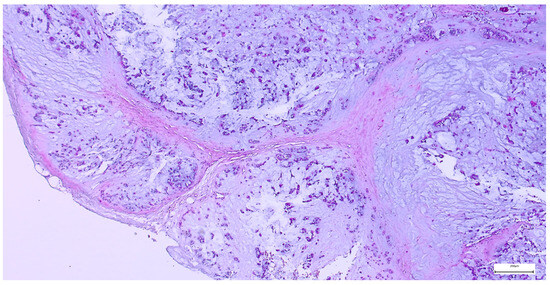

The capsule was incomplete in 67 cases (26.49%) of pleomorphic adenomas. Satellite nodules were documented as multiple nodules in 23 cases (9.09%), and as single nodules in 17 cases (6.71%). Pseudopodia were observed in 11 cases (4.34%), while both satellite nodules and pseudopodia were identified in 3 cases (1.27%) (Figure 5 and Figure 6).

Figure 6. Pleomorphic adenoma with intact capsule and pseudopodial extensions protruding into the surrounding parotid parenchyma (H&E staining, 5×).